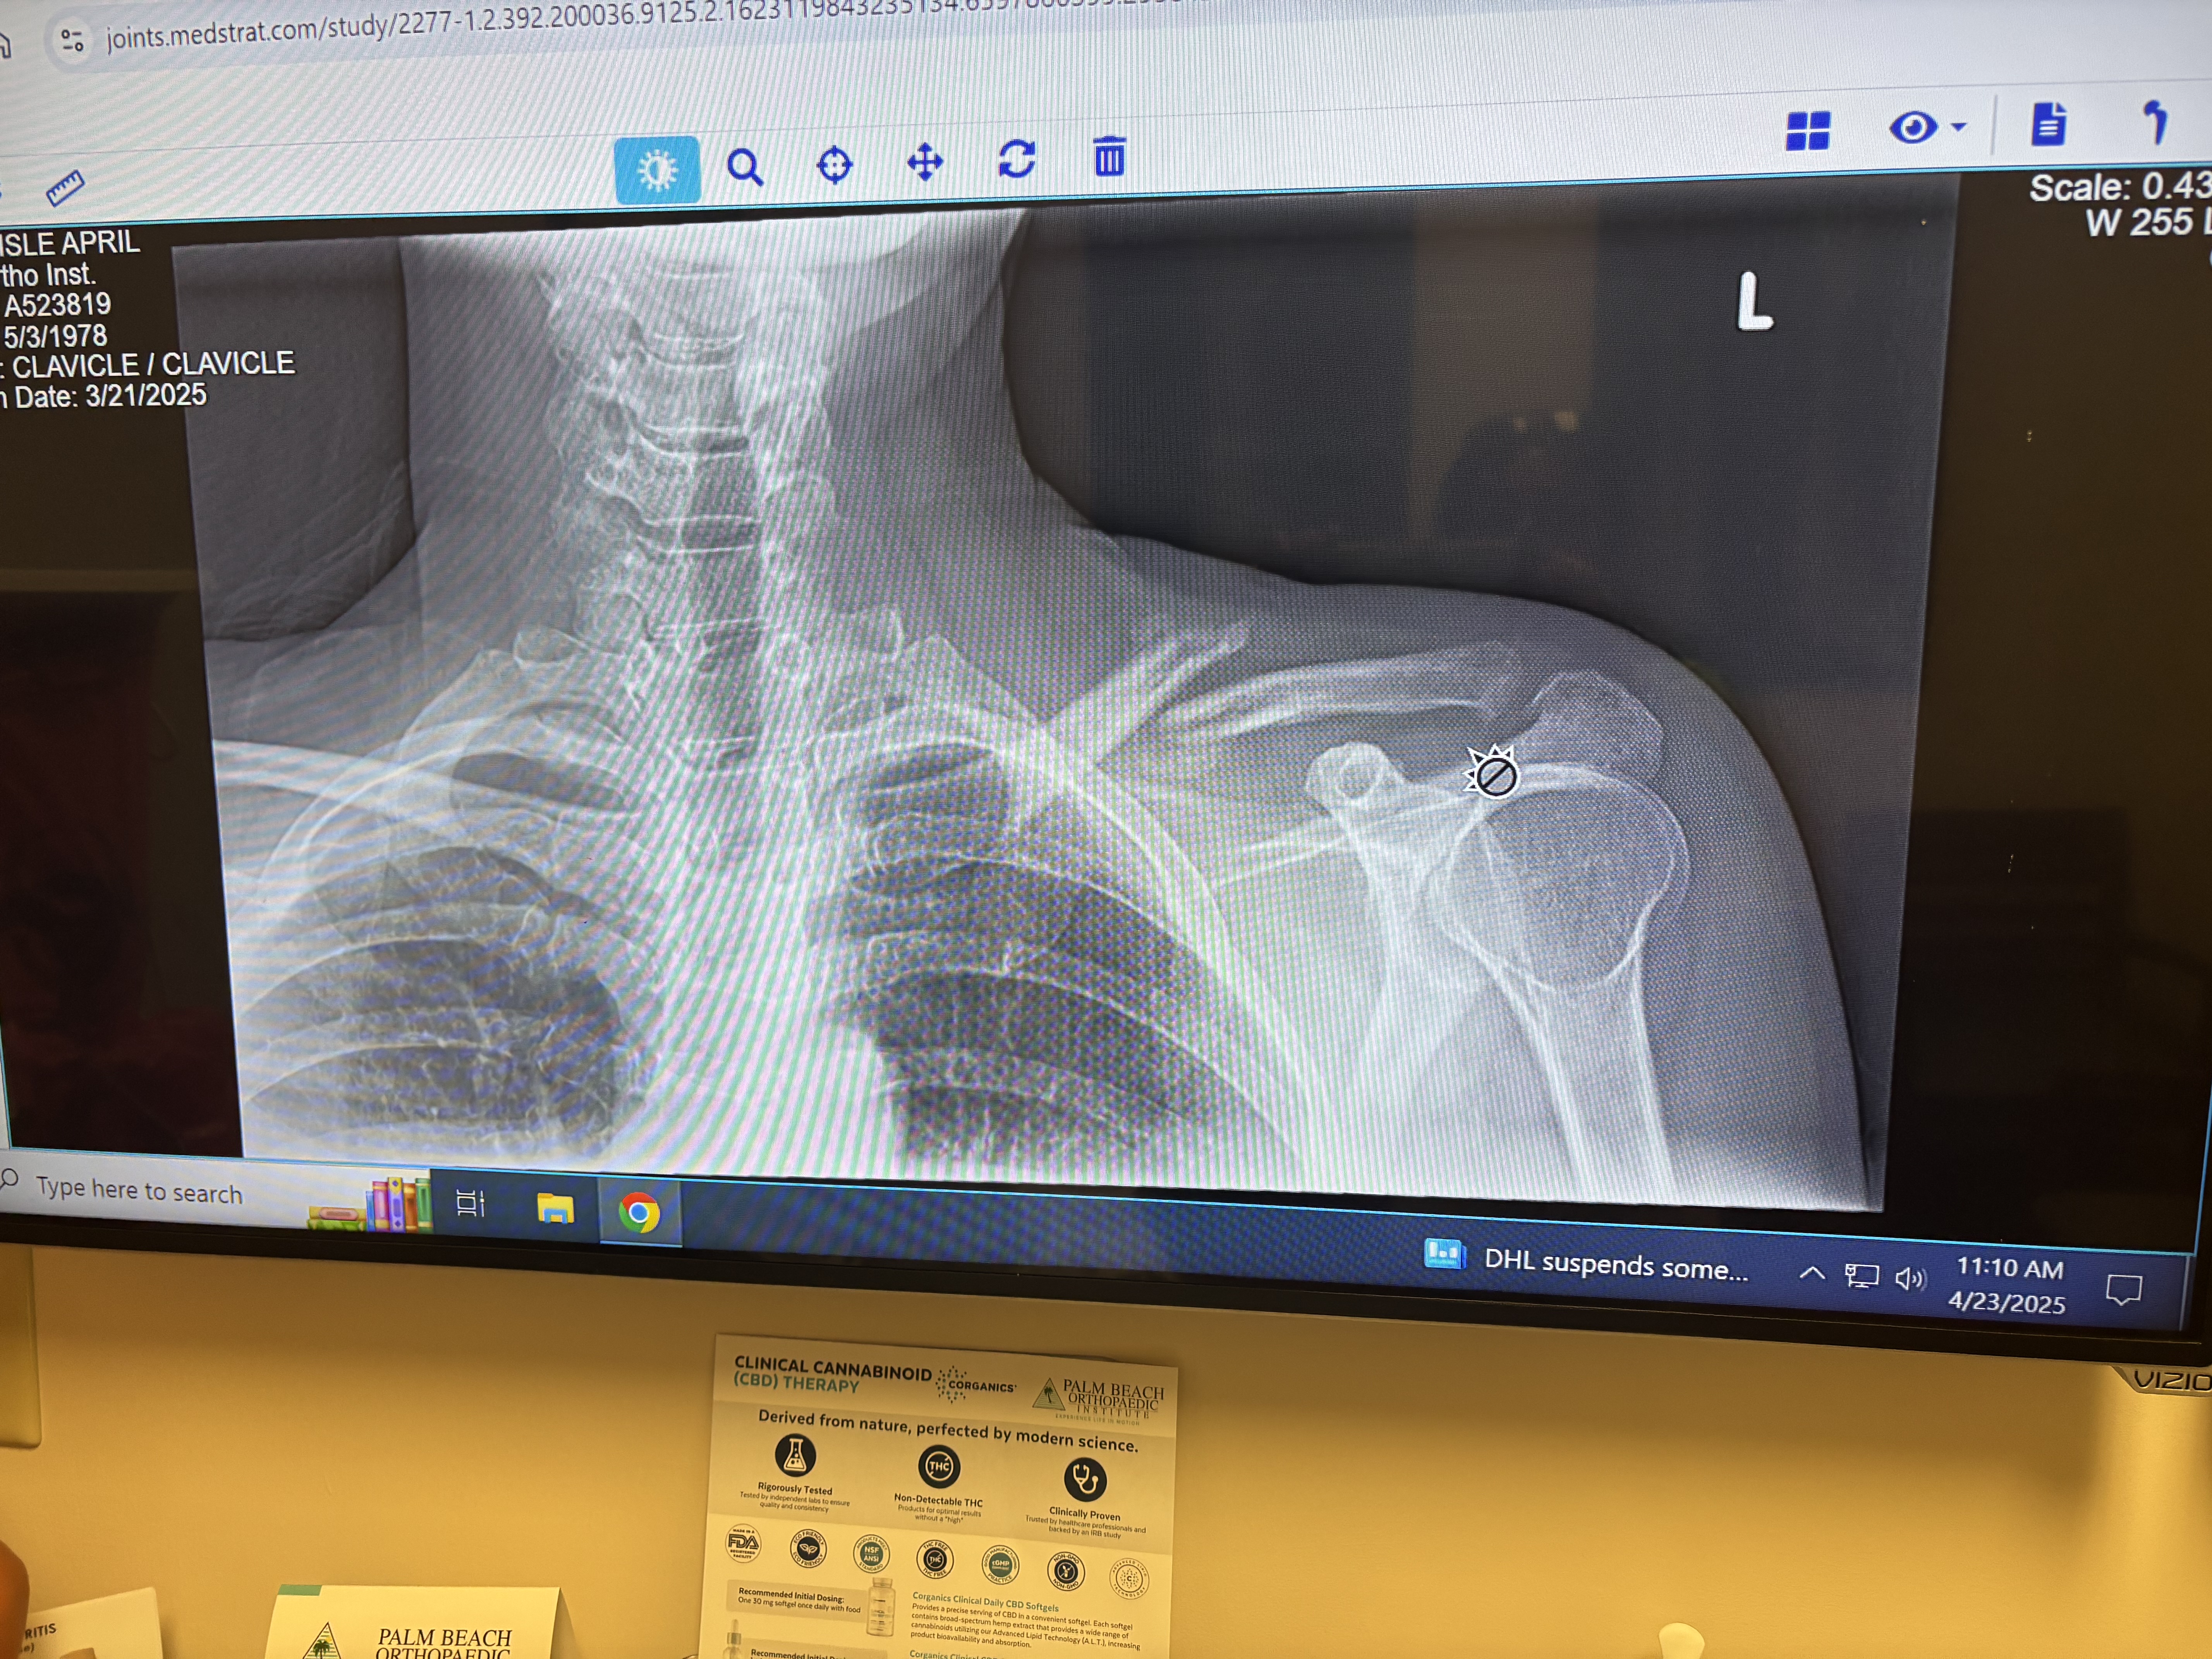

Hey friends and family, my name is April. I had a bad fall and broke my collarbone and kneecap. To try to avoid surgery, I'll be starting PT ASAP. I just started working again prior to the injury. I am asking for a little help to take some pressure off my sweetheart who has to carry me once again financially. Bills are piling up like crazy. Thank you kindly ❤️ I’ll be posting the pictures of the X-rays of my knee and shoulder very soon. My deductible is crushing us so I’ve opted to do PT at home for my knee. I’ll only have to go in for my shoulder. Thank you for your help, love and support!

thank you so much for your donations! I was able to get caught up with my health insurance and put some money towards the cc that I have maxed out using it for my doctor visits. I greatly appreciate your help. Please share my fundraiser with your friends and family. Any little amount helps greatly. I am so bummed to be out of work again. Staying positive and plugging along. Doctor said 6 weeks for my kneecap to heal. Shoulder Dr wants to see how I’m healing before we have to do surgery which would entail re breaking it, bone grafting along with a plate. After that heals , he would go back in to remove the plate. Praying I don’t have to go that route.

I saw the shoulder doctor today. Shoulder is slowly healing but I’m devastated as he said it will alway be messed up and slump down and forward. Also because of this and my knee , I feel again and have done something really back to my back. Having multiple severe spasms. I am going to see a spine specialist asap. Being in the car is super painful. Walking , but mostly sitting . Bummed. Thank you all for your support and kindness.